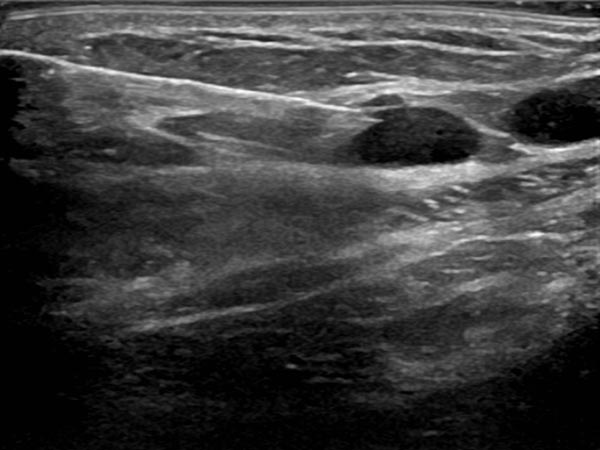

Circumscribed macrocystic malformation on the abdominal wall on ultrasound. Note the anechoic fluid in the thin-walled cystic spaces filled with liquid (lymph).